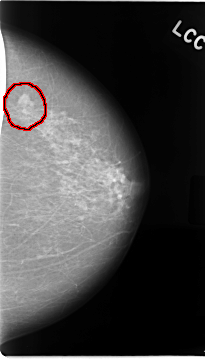

C_0018_1.LEFT_MLO

C_0018_1.LEFT_CC

FILE: C_0018_1.LEFT_CC.OVERLAY

TOTAL_ABNORMALITIES 1

ABNORMALITY 1

LESION_TYPE MASS SHAPE LOBULATED MARGINS MICROLOBULATED

ASSESSMENT 5

SUBTLETY 5

PATHOLOGY MALIGNANT

TOTAL_OUTLINES 1

BOUNDARY